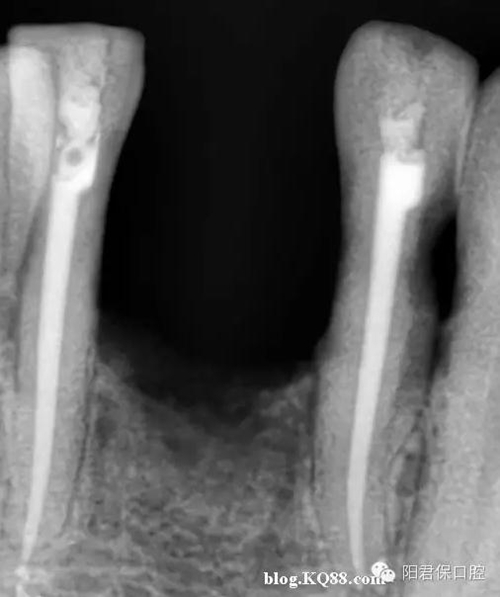

患者:姜XX 性別;女 年齡:65 根據(jù)齲壞程度、患者的癥狀、修復(fù)需要,且對(duì)收費(fèi)及牙髓處理均征得同意后第一次行右下4、5,左下4、5、6;第二次行左下2,右下2 ,右上7一次性根管治療術(shù)。

術(shù)后見右下4,左下4均有側(cè)支充填,且位置對(duì)稱,左下6近中根中部有側(cè)支;左下5、左下6遠(yuǎn)中根管均多個(gè)開口。

熱牙膠垂直加壓后有封閉劑和牙膠超填,但無(wú)術(shù)后反應(yīng)。